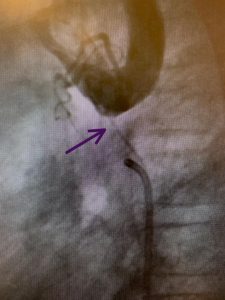

نجح الفريق الطبي في مركز الأمير سلطان لمعالجة أمراض وجراحة بالأحساء -بفضل الله – من إجراء قسطرة علاجية ناجحة لطفل بعمر سبع سنوات، كان يعاني من تضيق شديد في الشريان الأورطي النازل (شبه منقطع).

وقد تمكن فريق أطباء القلب في مركز الأمير سلطان لمعالجة أمراض وجراحة القلب التابع لتجمع الأحساء الصحي من تأكيد التشخيص، وبعد تقديم الشرح الوافي عن المخاطر للأهل وموافقتهم على الإجراء، أخضع المريض للقسطرة القلبية، وتم تركيب الدعامة المغطاة في الجزء المتضيق من الشريان الأورطي النازل، وفي اليوم الثاني تم تقييم المريض، والتأكد من انخفاض الضغط للحد المسموح به، وسمح بمغادرة المركز إلى المنزل وهو يتمتع بحالة صحية جيدة ومستقرة.